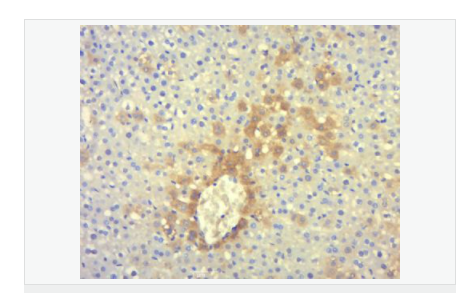

| 產(chǎn)品應(yīng)用 | ELISA=1:5000-10000 IHC-P=1:100-500 IHC-F=1:100-500 Flow-Cyt=1ug/Test IF=1:100-500 (石蠟切片需做抗原修復(fù)) not yet tested in other applications. optimal dilutions/concentrations should be determined by the end user. |